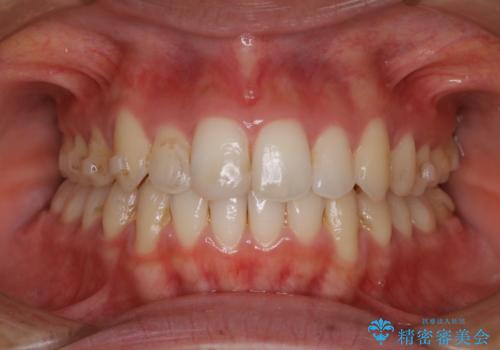

ぱっと見しっかり磨けているように見えますが、染だしをしてみると歯ぐきの境目などに磨き残しがあることがわかります。定期的に染め出しを行い、日々のブラッシングの癖や磨き残しを把握することで、改善するべきポイントが明確に発見されます。